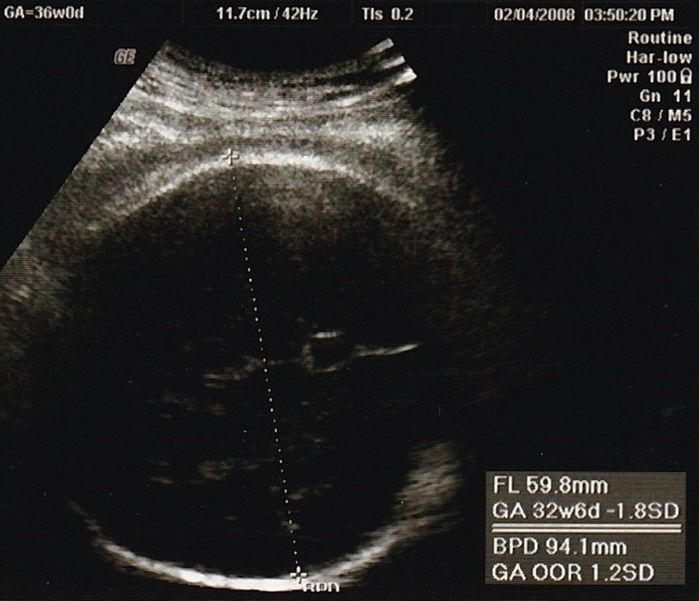

妊娠32週目のエコー写真

2000gを超えました。安心と同時に、体の重い状態がまだあと2カ月も続き、まだ大きくなるのかと思うと少し憂鬱に。体重も7kg以上増え助産師さんに注意されたものの、何か口に入れていないと気持ち悪くなるような状態で、つい食べ過ぎて自己嫌悪になることもありました。